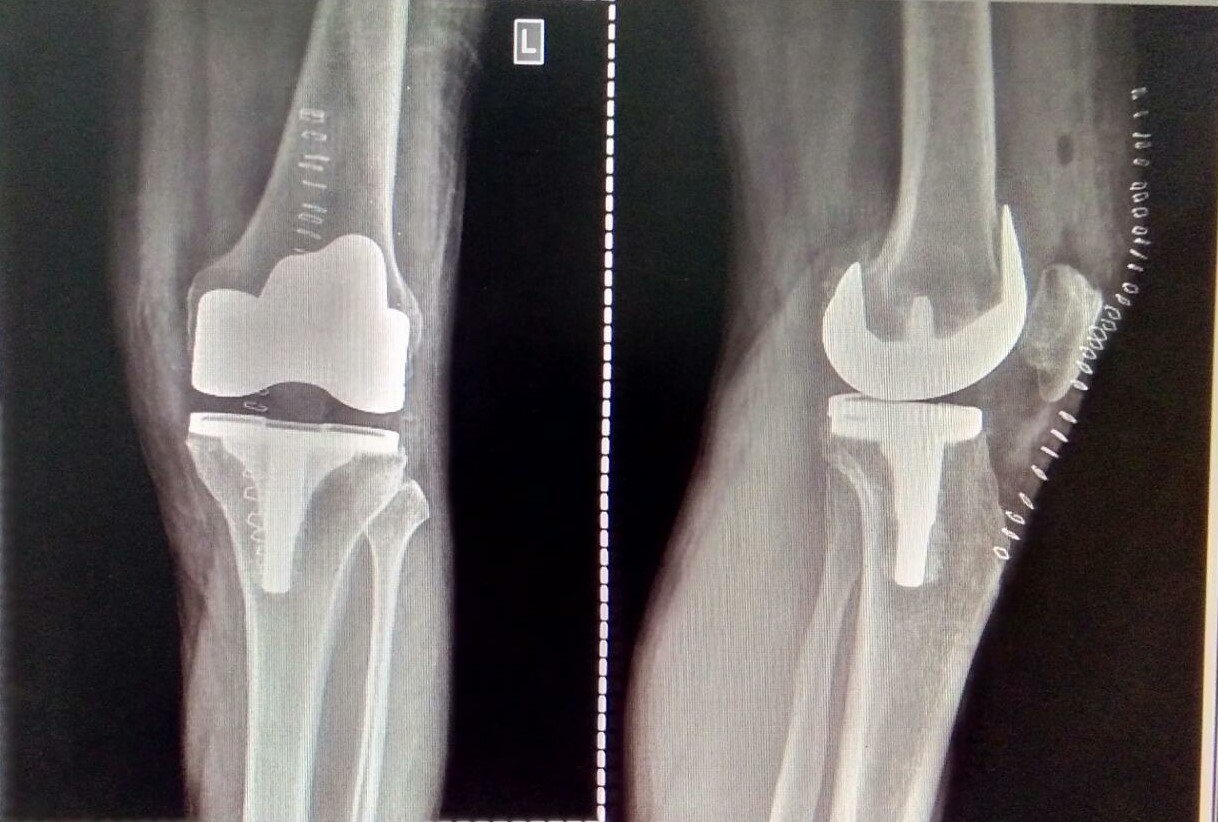

Knee and Hip Replacement